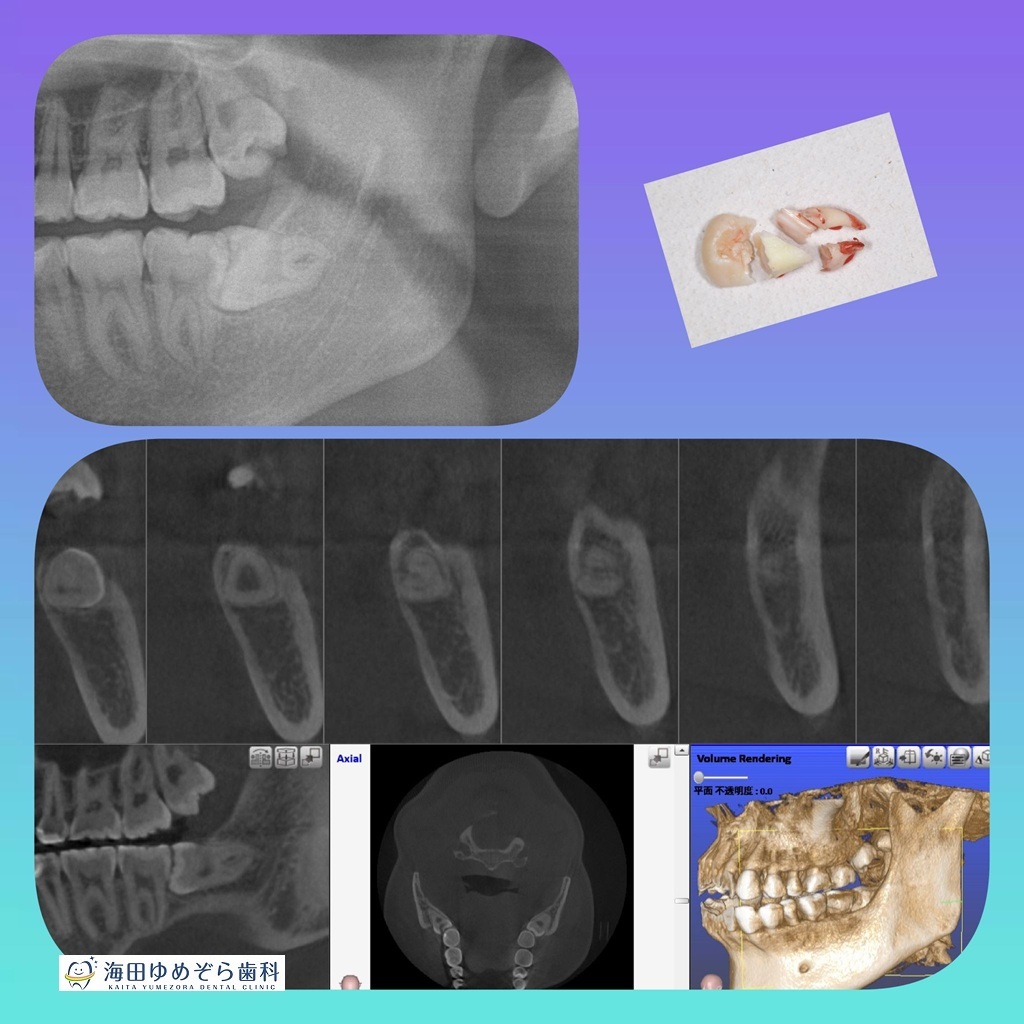

やさしさ...なのかな??ミュータンズ😈 #親知らず pic.x.com/q9t6ky8NtO